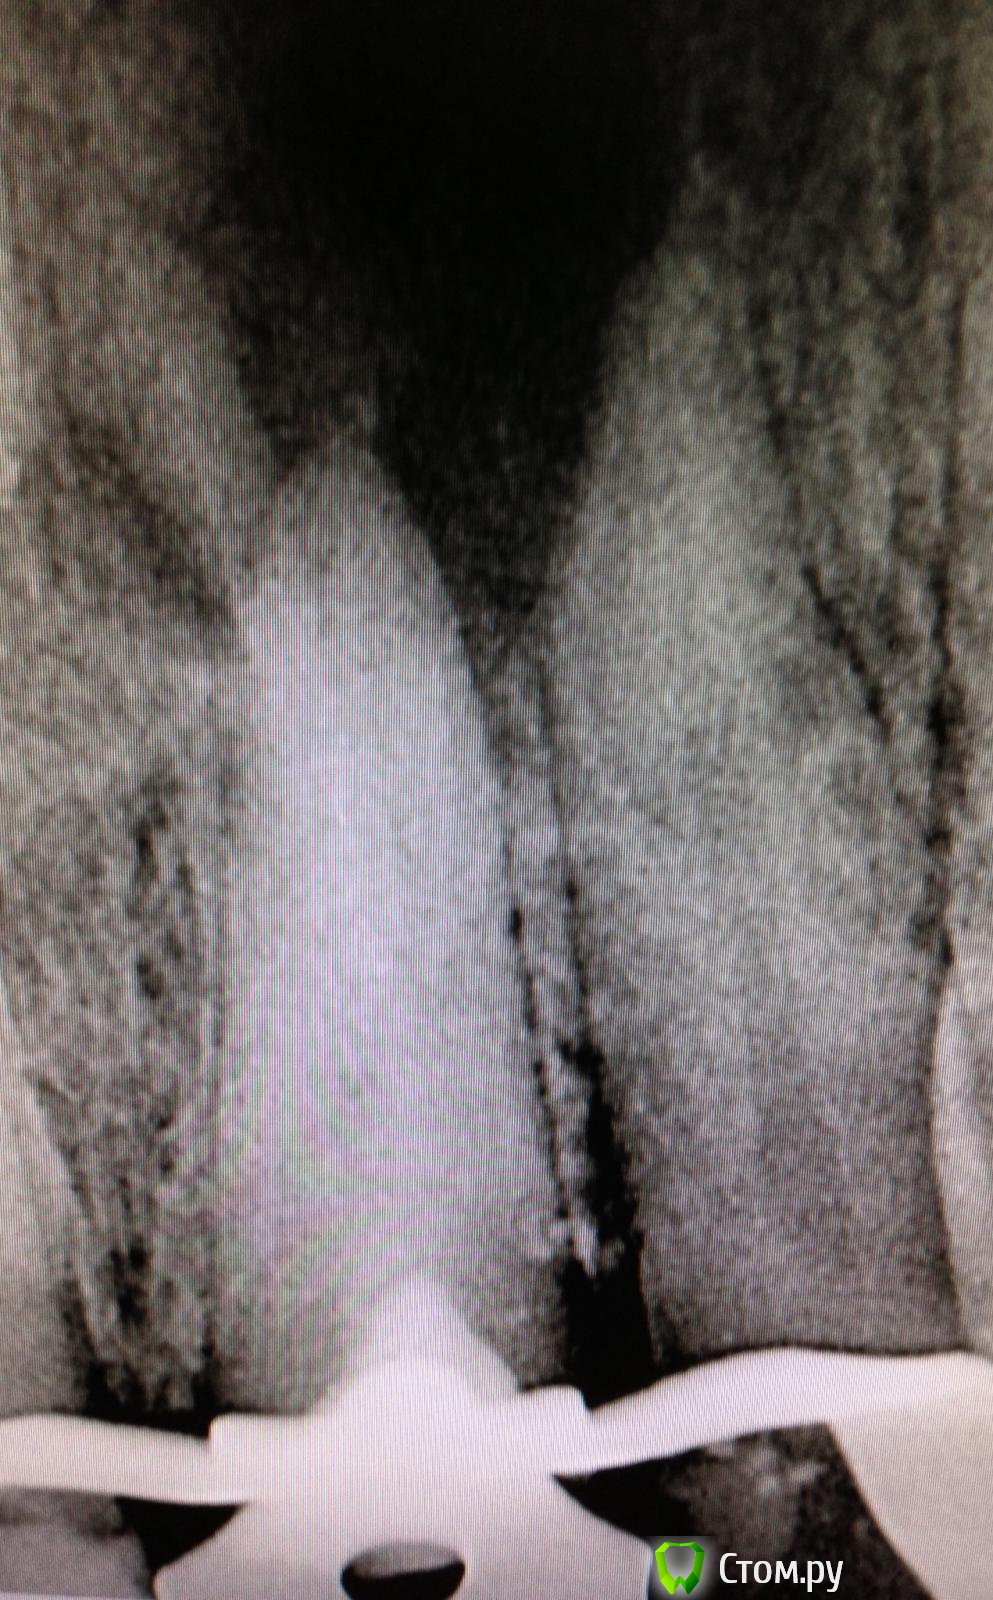

SSTi Опубликовано 30 мая, 2014 Автор Поделиться Опубликовано 30 мая, 2014 Пришла женщина со снимочком... Скололась старая реставрация. Зуб особо не беспокоит... Анестезия , коффер, минут сорок уз сюивал цемент рядом со штифтом, потом раскачал , и еще минут 15 выкручивал потихоньку.из канала течет экссудат. Ручними до 40.02. Протейперы машинные до f3. Гипохлор, уз,вода, эдта, хлоргексидин. Высушил. Кальций. Ссылка на комментарий